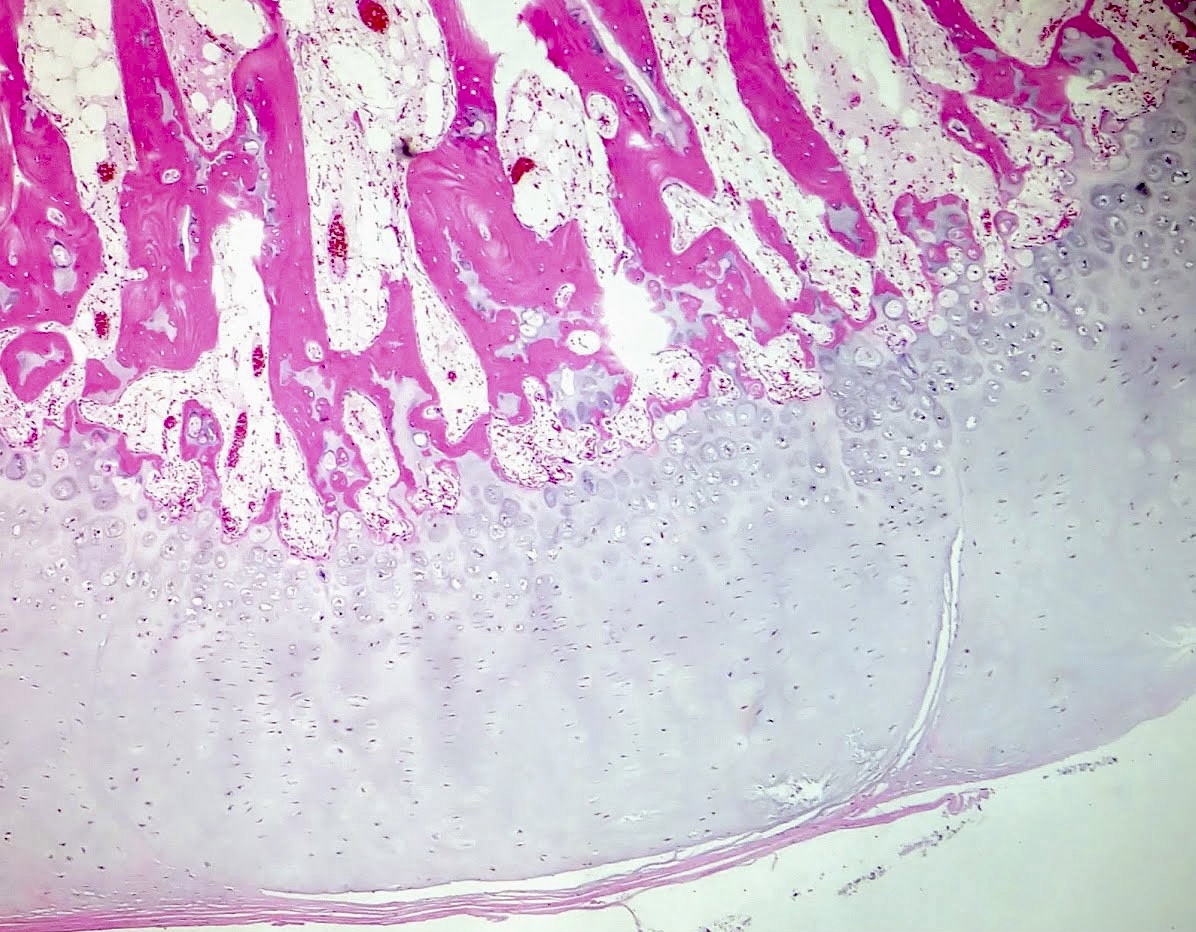

Microscopic (histologic) description

- Cap composed of mature hyaline cartilage with overlying fibrous perichondrium

- In young patients, transition between bone and cartilage cap resembles growth plate, showing endochondral ossification into mature bone; cartilage cap diminishes and may essentially be absent in older adults

- Marrow elements may be present within bony stalk; marrow space / cancellous bone contiguous with that of the native bone

Microscopic (histologic) images